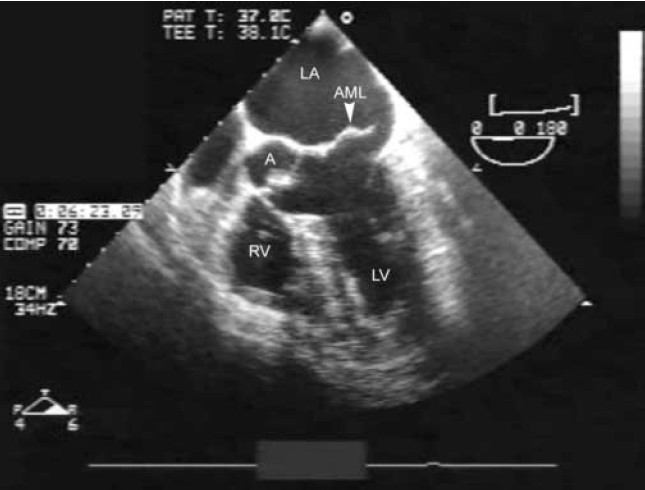

Double Valve Replacement For Acute Spontaneous Left Chordal Rupture

cardiothoracicsurgery.biomedcentral.com

cardiothoracicsurgery.biomedcentral.com

ruptured chordae mitral echocardiogram rupture transesophageal anterior chordal aortic leaflet incompetence chronic spontaneous acute